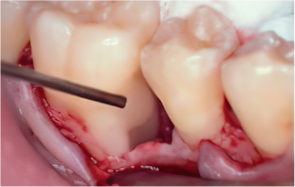

-

STEP 03

Removal of calculus and plaque